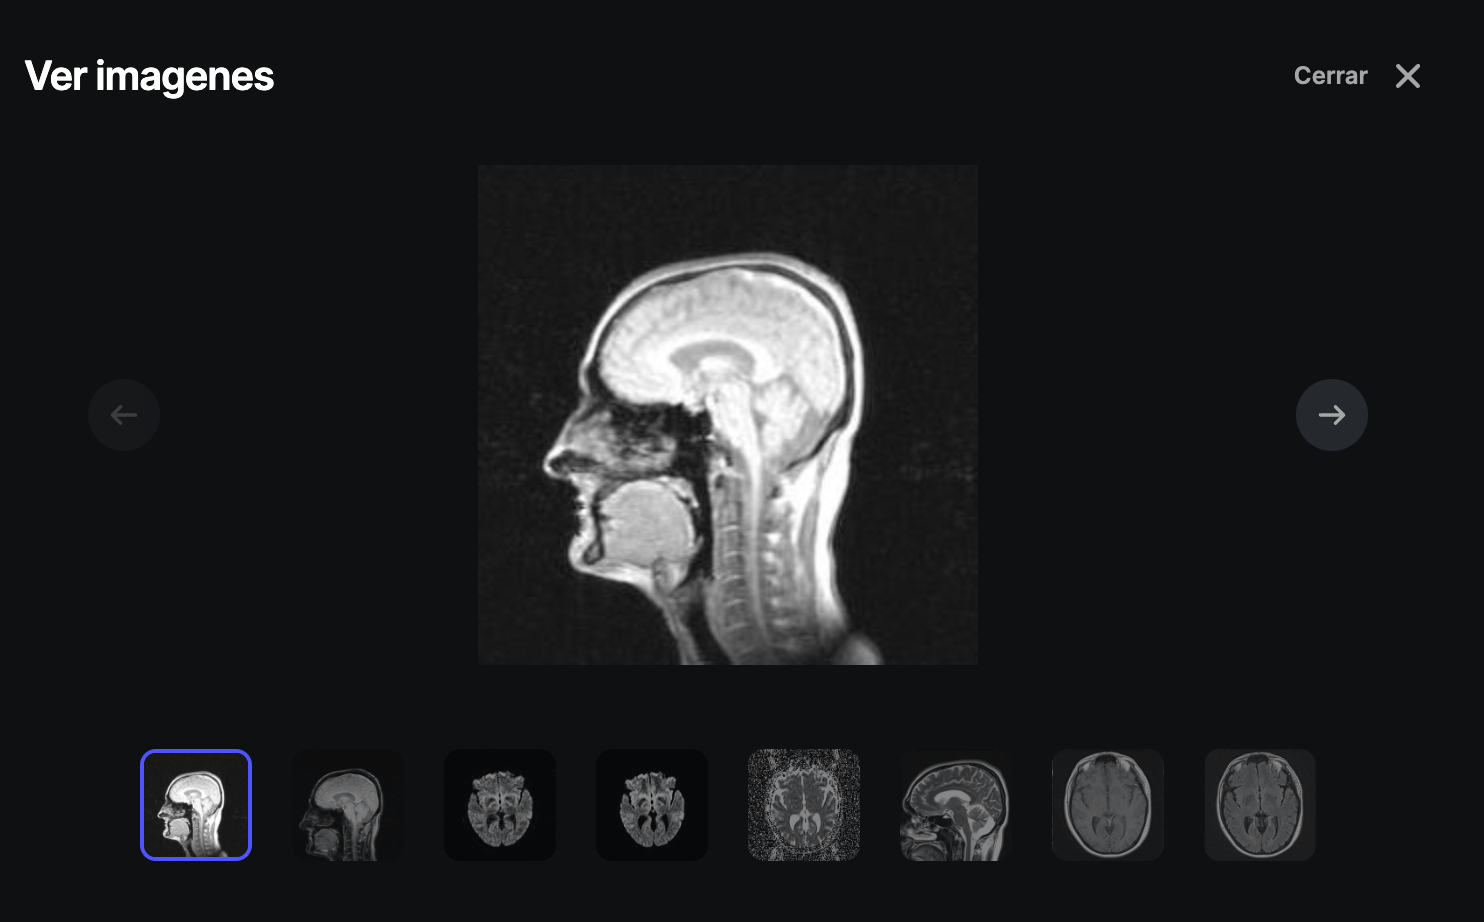

Vista previa:

Con esta opción, podemos abrir un pequeño visor que nos da un vistazo de las imágenes con las que cuenta el estudio como nos muestra la siguiente imagen: